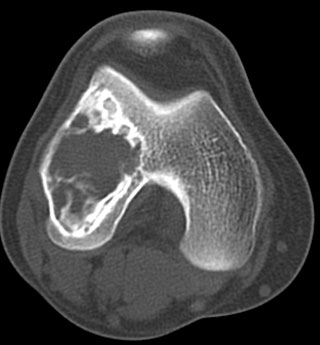

患者,女,32岁,因外伤后右膝疼痛而做ct检查.请大家讨论.有手术病检结果

股骨下端跨越骨骺、干骺端破坏性病变,内上方见多数斑片状钙化,并可见宽窄不一房隔,边缘硬化,无明显膨胀,关节面皮质连续,软组织内无肿块及钙化影。

考虑:软骨粘液样纤维瘤可能性大。

股骨下端跨越骨骺、干骺端破坏性病变,内上方见多数斑片状钙化或骨化,并可见宽窄不一房隔,边缘硬化,无明显膨胀,关节面皮质连续,无骨膜反应,软组织内无肿块及钙化影。

考虑:骨良性肿瘤病变----1成骨细胞瘤。2成软骨细胞瘤。3软骨粘液样纤维瘤。